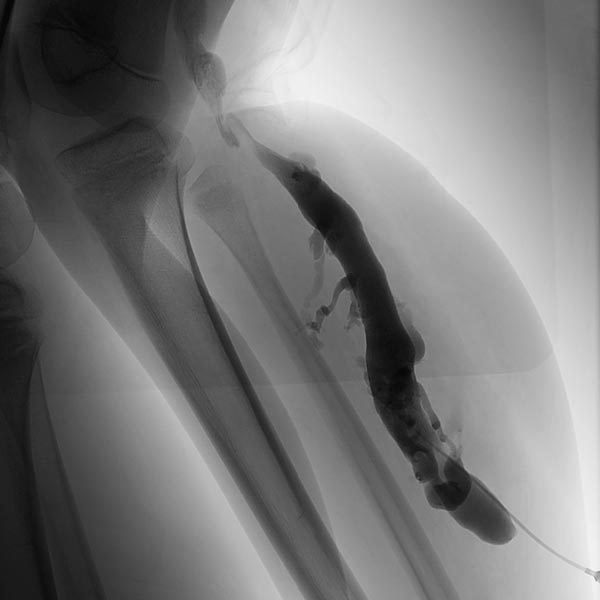

Phlebography after direct puncture of the venous malformation shows a large-lumen drainage vein communicating with the popliteal vein in the popliteal fossa. This must be occluded before sclerotherapy, otherwise the sclerosing agent could unintentionally dislocate through this communication and potentially cause thrombosis of the deep venous system of the leg and/or pulmonary embolism. In addition, there is an ongoing, increased risk of thromboembolism in this patient even outside of sclerotherapy, which can be significantly reduced by occlusion of the communication.

To occlude the vein, a large-lumen introducer sheath is first advanced via a guidewire. This sheath is used to insert the laser fiber and is advanced via the vein to the communication point in the popliteal fossa.

A laser fiber is advanced through this sheath for endovascular laser therapy. The heat of the laser beam causes massive irritation of the vein wall, which subsequently closes quickly. Thrombus formation immediately occurs around the laser tip.

After occlusion via laser fiber and contrast injection via the pulled-back introducer sheath, there is no more outflow of the contrast medium via the communicating vein. Thus the communication is successfully occluded. Only the venous malformation is still contrasted. This is now ready for sclerotherapy, as the sclerosing agent can no longer drain into the deep venous system of the leg.